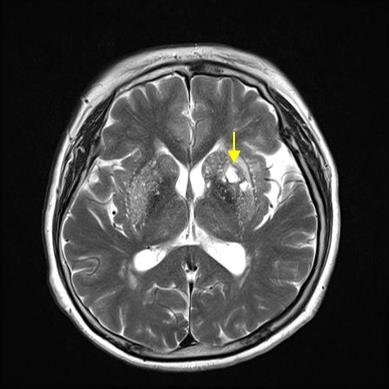

특별한 변화 없이 가만히 있다는데 땅이 움직이거나 주위의 사물이 돌아가는 느낌이 드는 등 어지럼증이 연속된다면 뇌경색 초기증상을 의문스러워해 볼 수 있습니다. 뇌경색으로 인해 혈액이 제대로 전달되지 못해 뇌가 정상적으로 작동하지 않아 생기는 증상이고요.